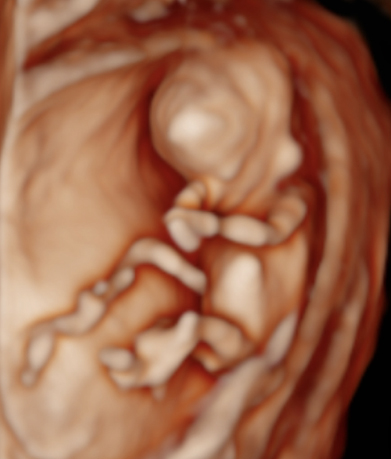

Dear future mother, we provide both basic and specialized ultrasound scans in pregnancy. We use Samsung’s state-of-the-art ultrasound systems and all our doctors are holders of Fetal Medicine Foundation certificates for all types of ultrasound examinations in pregnancy. We follow FMF protocols for fetal examinations and combine 2D with 3D ultrasound scan and assess even subtle anatomical details in order to obtain as precise a result as possible. Throughout the scan, we will keep you informed about the parts of fetal anatomy displayed on the screen. After the scan we will explain to you the results, prognosis and possible further management.

Our ultrasound scans are totally safe both for you and your baby.